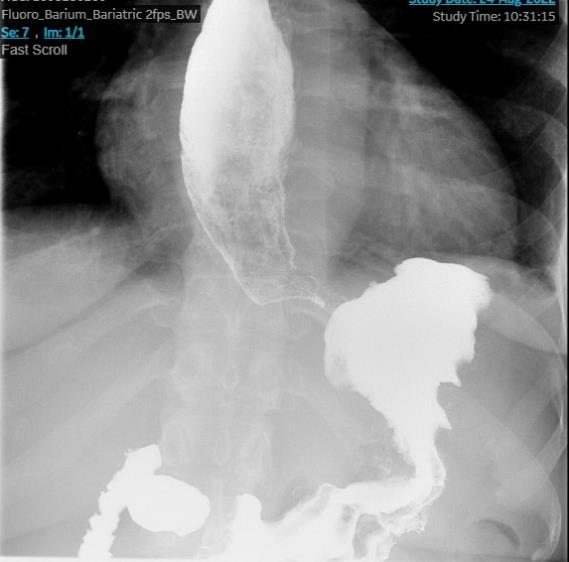

BURKITT LYMPHOMA INDUCED PSEUDOACHALASIA WITH DRAMATIC SYMPTOMATIC IMPROVEMENT POST-CHEMOTHERAPY

Marni H. Wilkoff1 , Emily S. Seltzer1 , Allison E. Wang1,2 , Bruno Almeida Costa1 , Bruce Gelman1

1Mount Sinai Morningside-West Hospitals, Icahn School of Medicine at Mount Sinai, New York, NY, United States;

2Mount Sinai Beth Israel Hospital, Icahn School of Medicine at Mount Sinai, New York, NY, United States 69